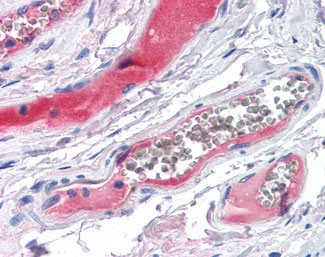

Anti-KLKB1 antibody IHC of human small intestine, vessels. |